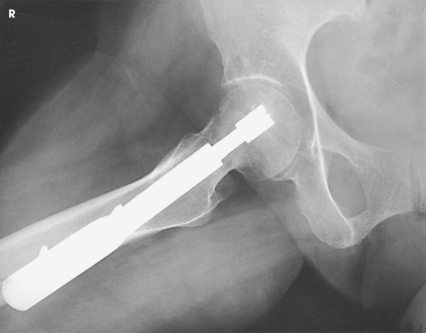

This projection is often called the cross-table or surgical-lateral projection.

Structures shown: The resulting image shows the acetabulum, head, neck, and trochanters of the femur (Fig. 7-37).